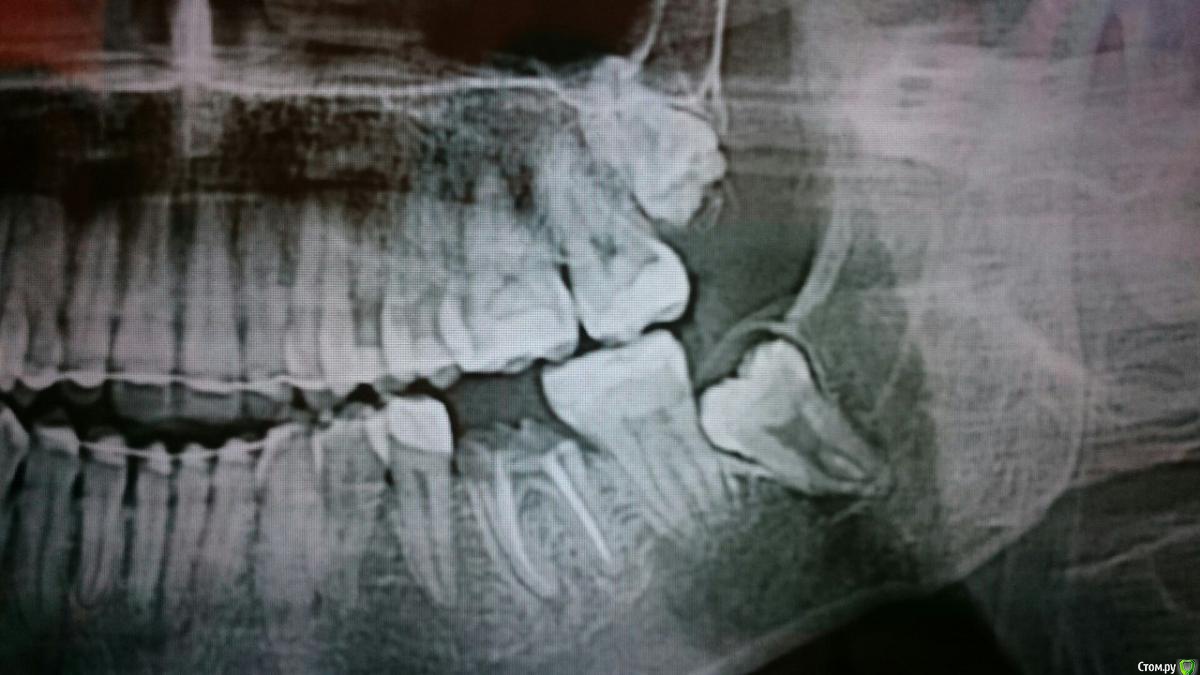

Libelle888 Опубликовано 27 апреля, 2017 Поделиться Опубликовано 27 апреля, 2017 Добрый день. Хотелось бы получить консультацию по поводу зуба мудрости. У меня их 3, все три не выросли, нижние упираются в соседние зубы, верхний лежит в сторону щеки. Правую нижнюю шестерку (корни) мне удалили прошлым летом. После этого стала ныть челюсть с той стороны. Врач сказал, что это 8ка стала на него давить, а тк зуб с нервом, соответственно он реагирует. Сказал что такие зубы удаляют только в стационаре... тк он очень глубоко и сидит на нерве... и вообще он бы их не трогал пока, а верхний он вообще сказал только в самом крайнем случае, тк он в гайморовой пазухе и это типа тоже сложная операция( У меня несколько вопросов:1) Есть ли такая вероятность, что 8 ка отодвинет 7-ку на пустое место и прорежется? Можно ли таким образом избежать ее удаления 2) По поводу верхнего зуба, если он все таки решит прорезаться , будет легче удалить, чем вырезать из десны? 2) Если все таки 100% удалять, действительно ли это настолько сложные зубы, что только стационар? Делают под местным обезболиванием или под общим?3) Могут ли от зуба мудрости воспалиться лимфоузлы под челюстью? Снимки прилагаю Ссылка на комментарий

Libelle888 Опубликовано 28 апреля, 2017 Автор Поделиться Опубликовано 28 апреля, 2017 может или нет будет видно на очном осмотре, у Вас кандидатов на причину боли слева, несколько а кто еще? А еще не подскажите, под зубами мудрости черное - это кисты? Ссылка на комментарий

red_butler Опубликовано 28 апреля, 2017 Поделиться Опубликовано 28 апреля, 2017 а кто еще? возможен пульпит в зубах с огромными пломбами А еще не подскажите, под зубами мудрости черное - это кисты? нет, это искажение снимка Ссылка на комментарий